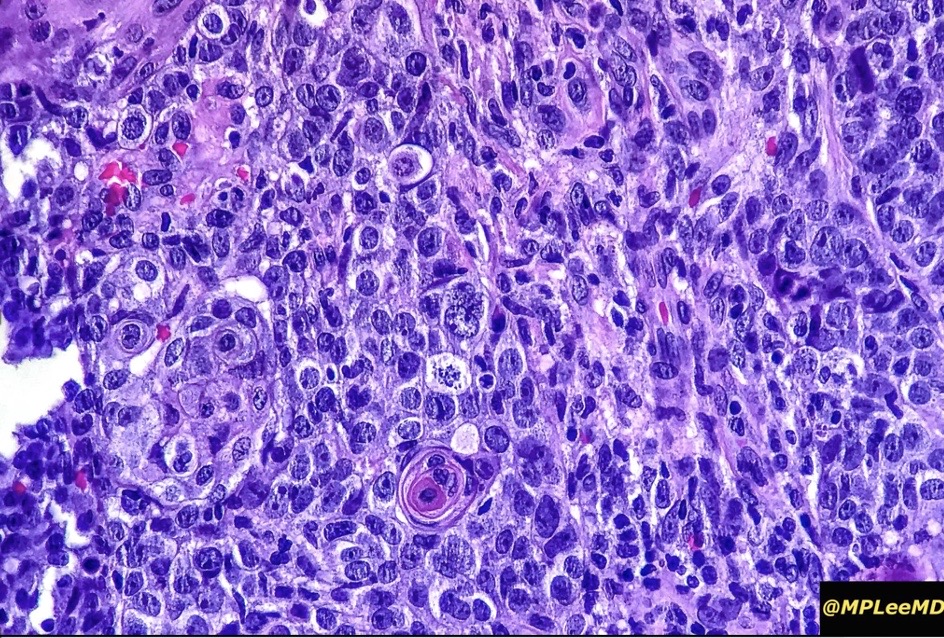

An exceedingly rare collision tumor composed of an admixture of squamous cell carcinoma/basal cell carcinoma/trichoblastoma respectively and melanoma. Although most appear to have behaved in a benign fashion, a malignant basomelanocytic tumor is illustrated below. More cases will be need to be stidies/published before the true biological behavior of this group of tumors can be satisfactorily elucidated. I think that complete excision should be the rule and a careful follow-up recomended.

Basomelanocytic tumor

Squamomelanocytic tumor